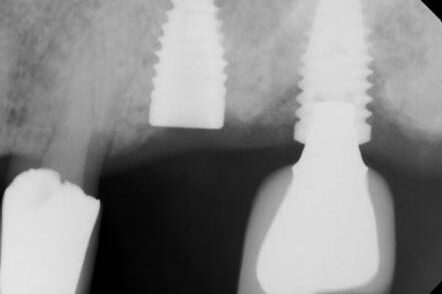

The following case involves a Nobel Active 3.0 in the #4 site. The case was in function for just over 2 years when the abutment screw fractured. There was a prior recovery effort with a Cavitron ultrasonic unit. As the abutment and crown had been lost, identification was not possible. When the patient was examined in our office, the fragment was non-mobile and located below the first implant thread. To safely retrieve this Type IV screw fragment, mobilization was required by using a concentric retrieval technique.

When an ultrasonic instrument is used internally in an implant, the case is often complicated as the ultrasonic energy can trough and basically hammer weld the screw and implant threads together. Often, a potentially mobile fragment, as described in the Types I and III descriptions above can easily be converted to a non-mobile fragment. At this point in the case the hope is the thread destruction is limited, and the fragment can be retrieved with concentric drilling and a screw extractor. If not, then progression to a complete drill out is required. The initial steps are the same, so a custom precision drill guide was set up, and the fragment was progressively drilled. As this is a M1.4 screw, the maximum sized bore to avoid threads is the predrill size of 1.1mm. For a screw extractor to be functional and have some screw to engage into a bore, the screw side wall has to have enough thickness to resist flaring when the screw extractor is engaged. The drilling progression, ending in .6mm, was used as documented below. These photographs are routinely taken to monitor the process to ensure the bore is positioned concentric as intended. There is very little room for error.

This drilling progression, from left to right, starts with a spot drill to help guide the .6mm drill to start concentrically. Next, a photo to confirm the position of the .6mm drill. Third, a progress photograph of the .6mm drill. Last, the .6mm bore has penetrated through the end of the screw fragment.

The above sequence photographed at 25x is routine and illustrates the control possible and necessary to achieve this result. A drilling protocol with less precision either in tooling or visualization can lead to severe complications. Fortunately, when a .6mm custom screw extractor was engaged the fragment cooperated and was retrieved, circumventing a complete drill out procedure as will be described in a following case.